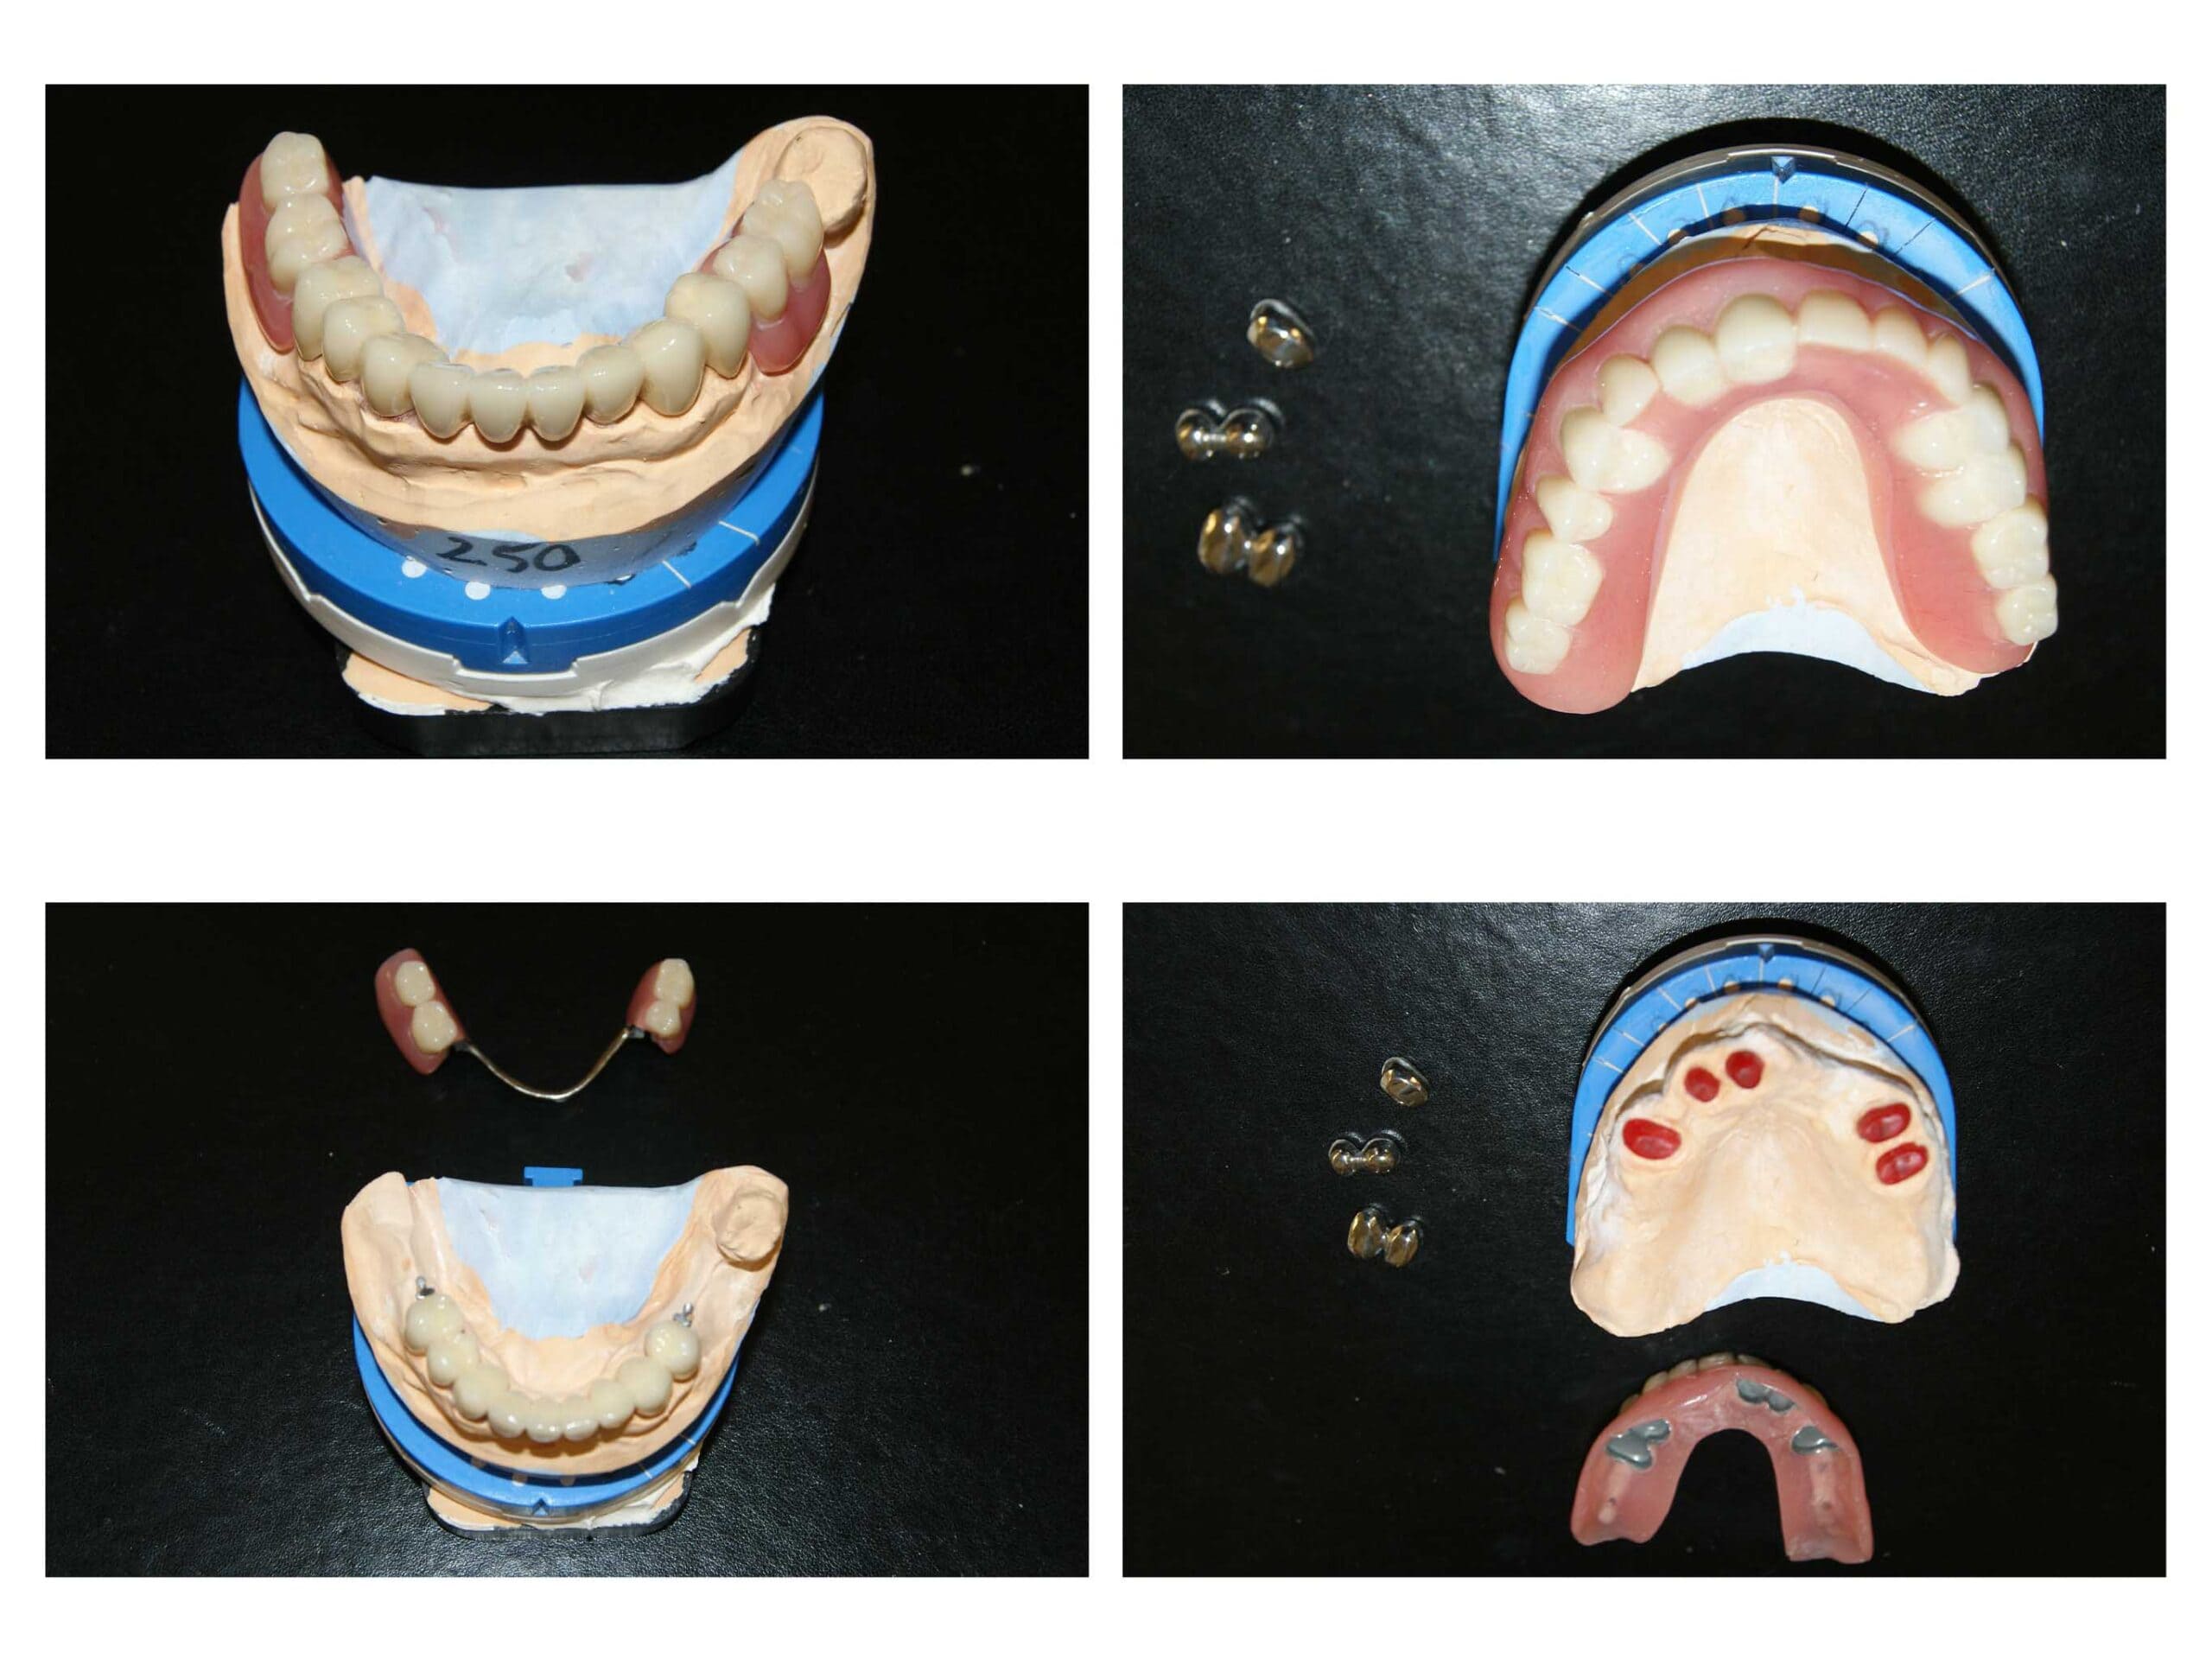

Proteza telescopată  și proteză scheletată aplicate pe dinții tratați corect! Execuția riguroasă oferă stabilitate excelentă.